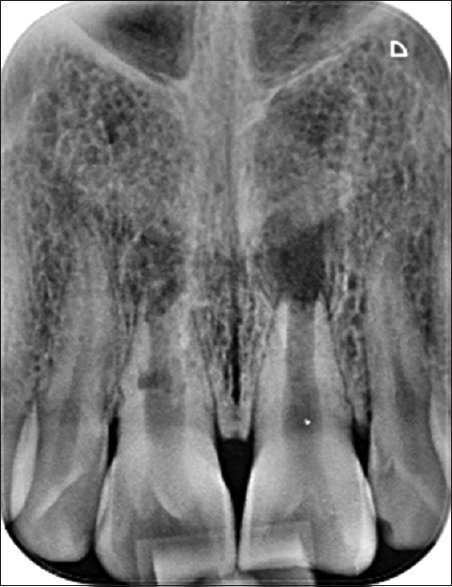

再生牙髓治疗是治疗牙尖开放坏死的一种权宜之计。再生牙髓治疗领域的临床研究取得了可喜的成果。本病例系列的主要目的是介绍再生牙髓治疗的影像学和临床表现。

Regenerative endodontics is an expedient therapeutic strategy for necrotic teeth with open apex. The promising result of clinical research in the regenerative endodontic treatment field is published. The main goal of this case series is to present the radiographic and clinical findings of the regenerative endodontic procedure.